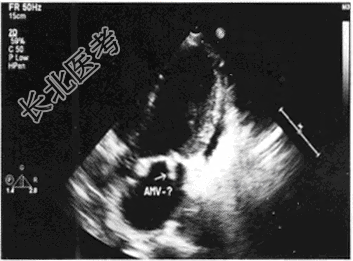

- 单项选择题患者,青年女性, 发热、畏寒、出汗数日就诊,查体发现二尖瓣区杂音, 如图为收缩期心尖五腔超声图像,该疾病最可能的诊断为

C、二尖瓣赘生物